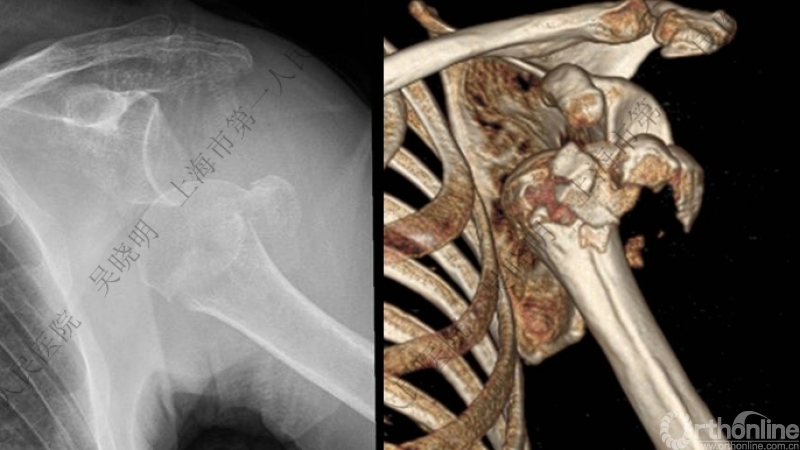

本组医源性骨折患者的影像学特点

均伴有大结节骨折;

可伴有外科颈骨折;

肱骨头可内移至喙突下;

肱骨头外翻畸形。

骨折线可以延伸到肱骨头

必要时进一步CT检查

肩关节前脱位合并大结节骨折&肱骨头外翻:外翻压缩型(Neer 分型)

对这型骨折进行手法复位会导致肱骨头和肱骨干之间的连续性消失。肱骨头和肱骨干之间连续性尚存,肱骨头前脱位(Robsion 3b)

外翻压缩型肱骨近端骨折

钢板固定